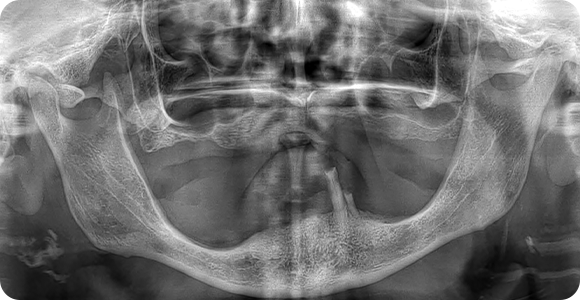

Öncesi & Sonrası